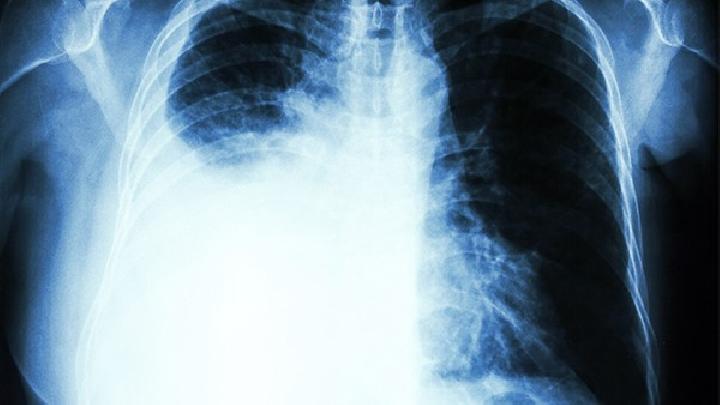

气胸